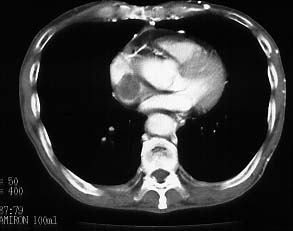

CaseYW01

- Age/Sex: 50M

- Chief Complaint: 頭痛,発汗過多,動悸,体重減少

- Clinical

Course: アルコール性肝炎にて経過観察中。最近1年間、高血圧症の診断で降圧薬を内服している。

- Lab. Data: 末梢血中濃度 Epinephrine 43 pg/ml (基準値 0-80),

Norepinephrine 31400 pg/ml (基準値 90-420), Dopamine 122 pg/ml

(基準値 0-30)

- Images:

- X-CT

- 131I MIBG,

48h

123I

MIBG, 24h

123I

MIBG, 24h